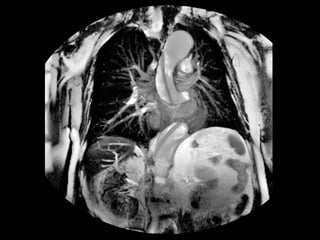

• #63 Ösophagus-Monokontrast mit wasserlöslichem Kontrastmittel (100 ml Peritrast®). Kontrastmittelaustritt im distalen Ösophagus links dorsolateral in die Pleurahöhle ( Pfeil )